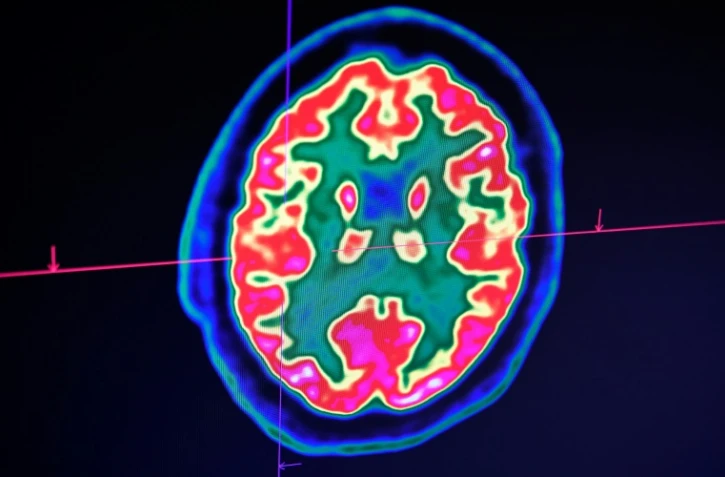

À l'occasion de la journée mondiale de l'AVC, ce vendredi 29 octobre 2021, les associations France AVC Réunion et Bouzanou se mobilisent pour mener des actions de prévention primaires auprès du plus grand nombre de personnes possibles sur le territoire. Ils interviendront auprès des Réunionnais dans les rues, les grandes surfaces ou encore, dans les transports en commun. Ces opérations de sensibilisations se poursuivront jusqu'à demain, samedi 30 octobre 2021. Nous publions ici le communiqué de presse de France AVC Réunion et Bouzanou. (Photo d'illustration)